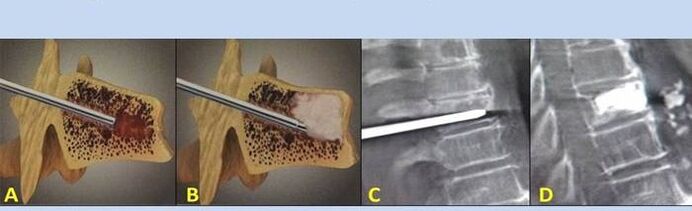

- Nukleoplastika – tarpslankstelinio disko šerdies pašalinimas. Operacija sumažina spaudimą nervų galūnėms.

- Punkcinė vertebroplastika – slankstelių stabilizavimo metodas. Procedūros metu gydytojas kauliniu cementu užpildo stuburo ertmes.